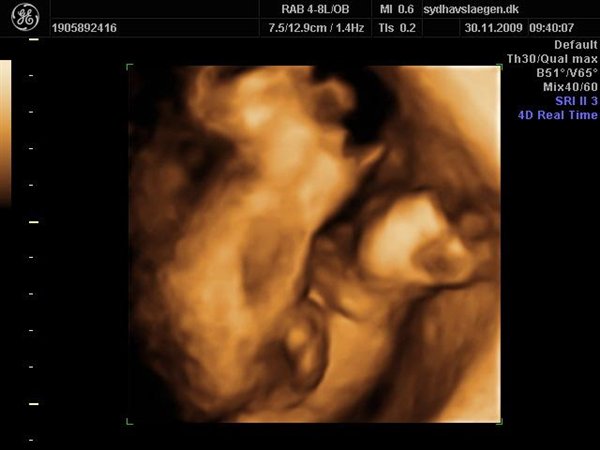

Da jeg snakkede med hende i dag sagde hun at fra uge 27 til og med uge 31 var det bedste tidspunkt at få det gjort....

Vi skal give 1400 kr for 45 minutters total gennem scanning, hvor hun fortæller, undersøger babyen fra top til tå, laver vægtskøn også får vi billeder og dvd med hjem.... Og ja det er da mange penge, men min forlovede har haft en masse vikar timer den her mdr, også sagde han at han syntes vi skulle bruge de penge på noget vi normalt ikke ville have gjort. Han sagde egentlig at jeg kunne gå ud og shoppe for dem, men jeg har termin om ti uger, så gider ærlig talt ikke bruge penge på nyt graviditets tøj, så hellere det her som vi egentlig havde valgt fra pga prisen, men som vi begge to rigtig gerne vil....